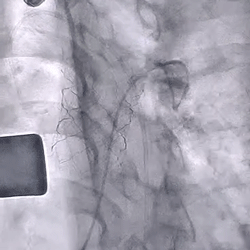

术前造影(可见大量反流) 术后造影(无反流)

患者男性,17岁,出生后2月因肺动脉瓣重度狭窄合并三尖瓣重度反流行外科手术重建右室流出道,2年前因三尖瓣反流加重行三尖瓣成型手术,此次入院前心超提示肺动脉瓣中重度反流。术前影像学重建显示提示患者肺动脉干明显增宽,瓣膜的固定成为了手术难点,经过术前多团队的缜密分析讨论,决定通过外科环缩肺动脉来解决这个问题。1月29日上午,复旦大学附属儿科医院的心血管杂交手术室内,心外科、心内科、麻醉科和心超室的各路专家们齐聚一堂,一起为本次多学科联合新技术手术保驾护航。儿科医院心血管中心主任、知名先心外科专家贾兵教授主刀,心内科主任刘芳教授精准定位,在心导管造影和食道心超的双重精确引导下,贾兵教授经由右心室表面穿刺准确地将30#介入肺动脉瓣放置到肺动脉的预定位置,同时环缩肺动脉,缝合固定支架瓣膜。造影和心超均显示肺动脉支架瓣膜功能完好,无瓣周漏及中央返流。实际瓣膜植入释放时间仅用了不到20分钟。术后当天患者就脱离了呼吸机,目前心功能恢复良好。